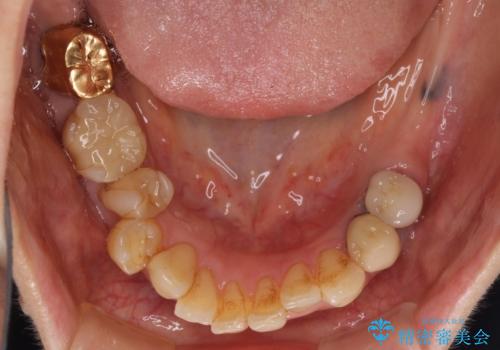

- 奥歯が痛いことを主訴にご来院された患者様です。入院してしまい、治療を2年間放置してしまったとのことでした。

左上は、抜歯とブリッジ治療を行いました(抜歯前に医師と対診)。

左下は、現在も抗がん治療を続けているため、観血的処置(インプラントなどの外科)はなるべく避けたいとのことで入れ歯を希望されました。それに伴い、入れ歯を支える歯のクラウンやりかえも行いました。

患者様はインプラント等の外科処置は希望されなかったため、セラミックと義歯で治療を行いました。

義歯を製作する際は、支えとなる歯の治療も同時に行うことで、義歯の製作が容易になります。

今回もそのように製作したところ、適合がよく安定のよい義歯になりました。患者様本人も使っていて全く痛くないとのことで、追加の調整もなく使用して頂いてます。患者様には、大変満足して頂きました。